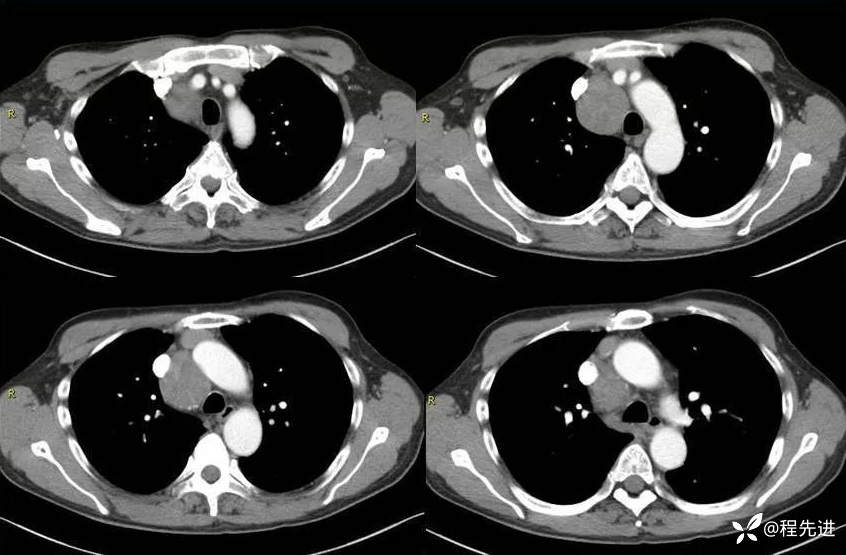

CT

增强动脉期横断位